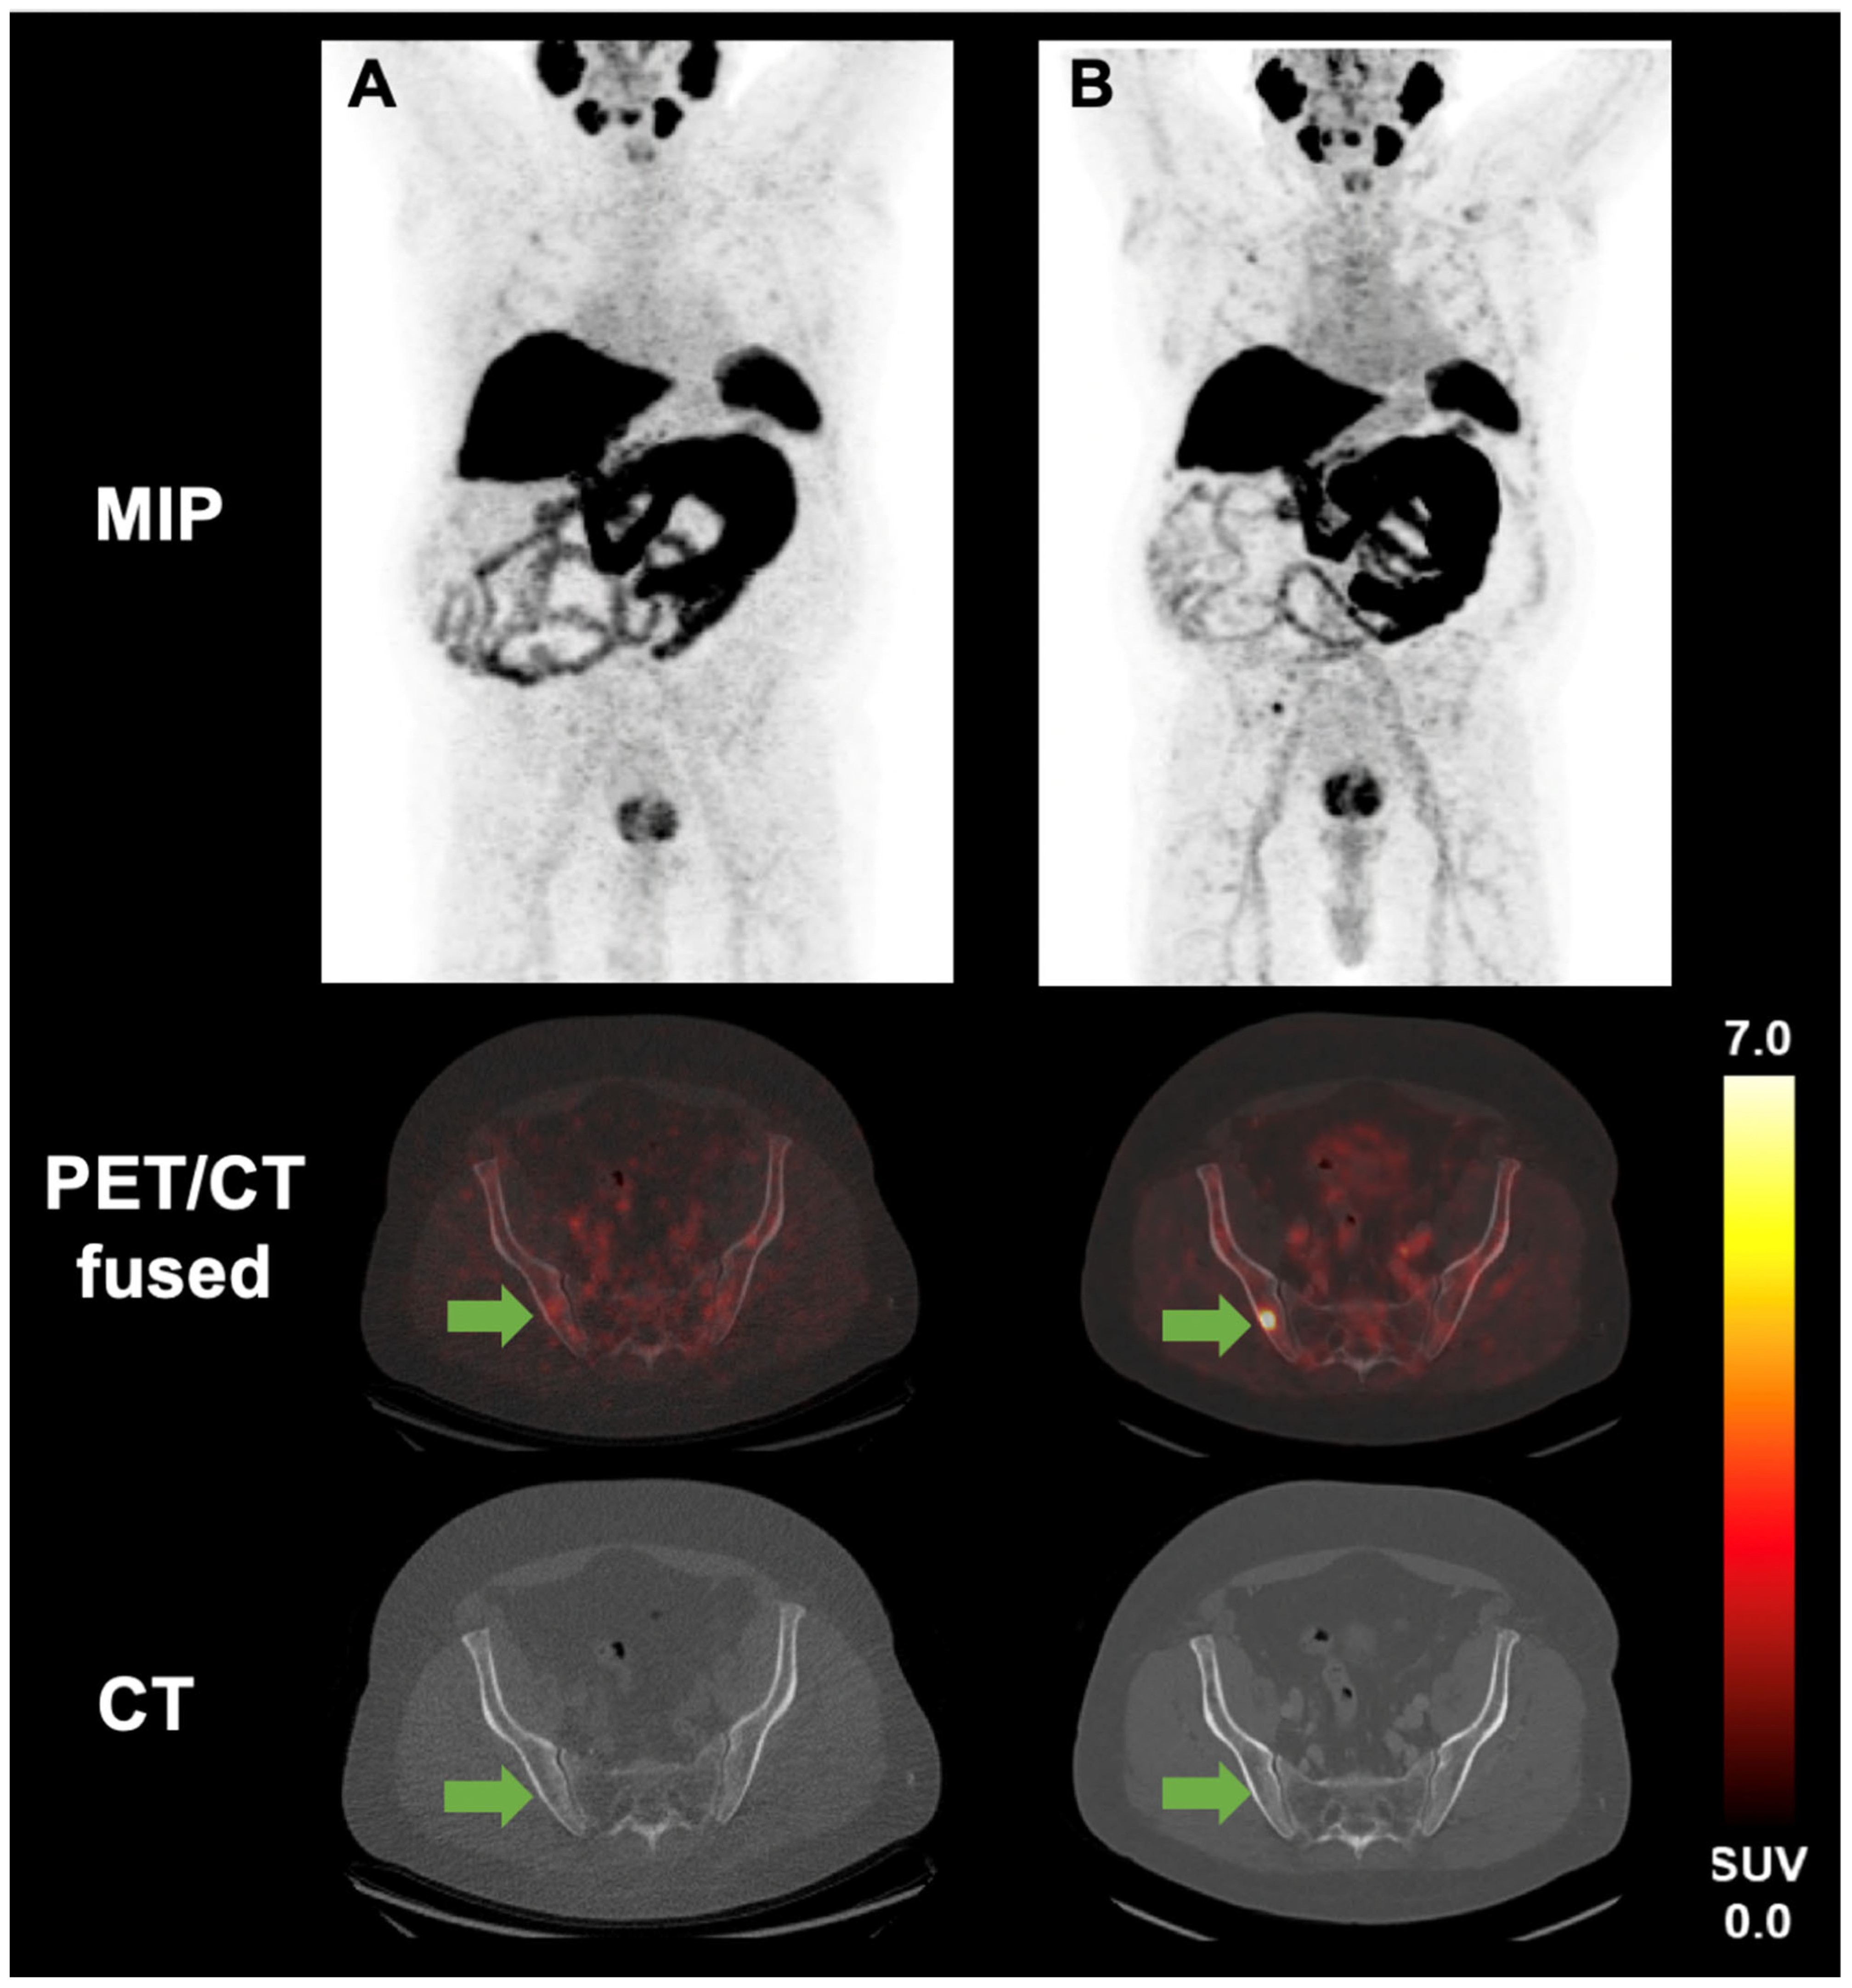

- Mittlmeier, L.M.; Unterrainer, M.; Rodler, S.; Todica, A.; Albert, N.L.; Burgard, C.; Cyran, C.C.; Kunz, W.G.; Ricke, J.; Bartenstein, P.; et al. 18F-PSMA-1007 PET/CT for response assessment in patients with metastatic renal cell carcinoma undergoing tyrosine kinase or checkpoint inhibitor therapy: Preliminary results. Eur. J. Nucl. Med. Mol. Imaging 2021, 48, 2031–2037. [Google Scholar] [CrossRef]

- Mittlmeier, L.M.; Unterrainer, M.; Todica, A.; Cyran, C.C.; Rodler, S.; Bartenstein, P.; Stief, C.G.; Ilhan, H.; Staehler, M. PSMA PET/CT for tyrosine-kinase inhibitor monitoring in metastatic renal cell carcinoma. Eur. J. Nucl. Med. Mol. Imaging 2020, 47, 2216–2217. [Google Scholar] [CrossRef]